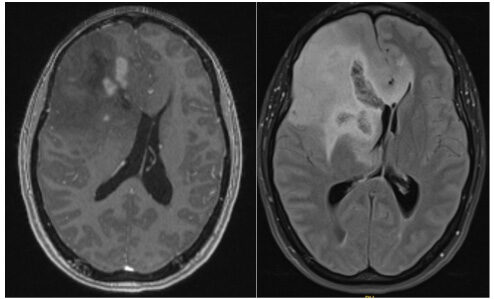

Image 1 (left): MRI of a grade IV glioma in the left occipital lobe

Image 2 (right): MRI showing Grade I pilocytic astrocytoma in the right frontal lobe